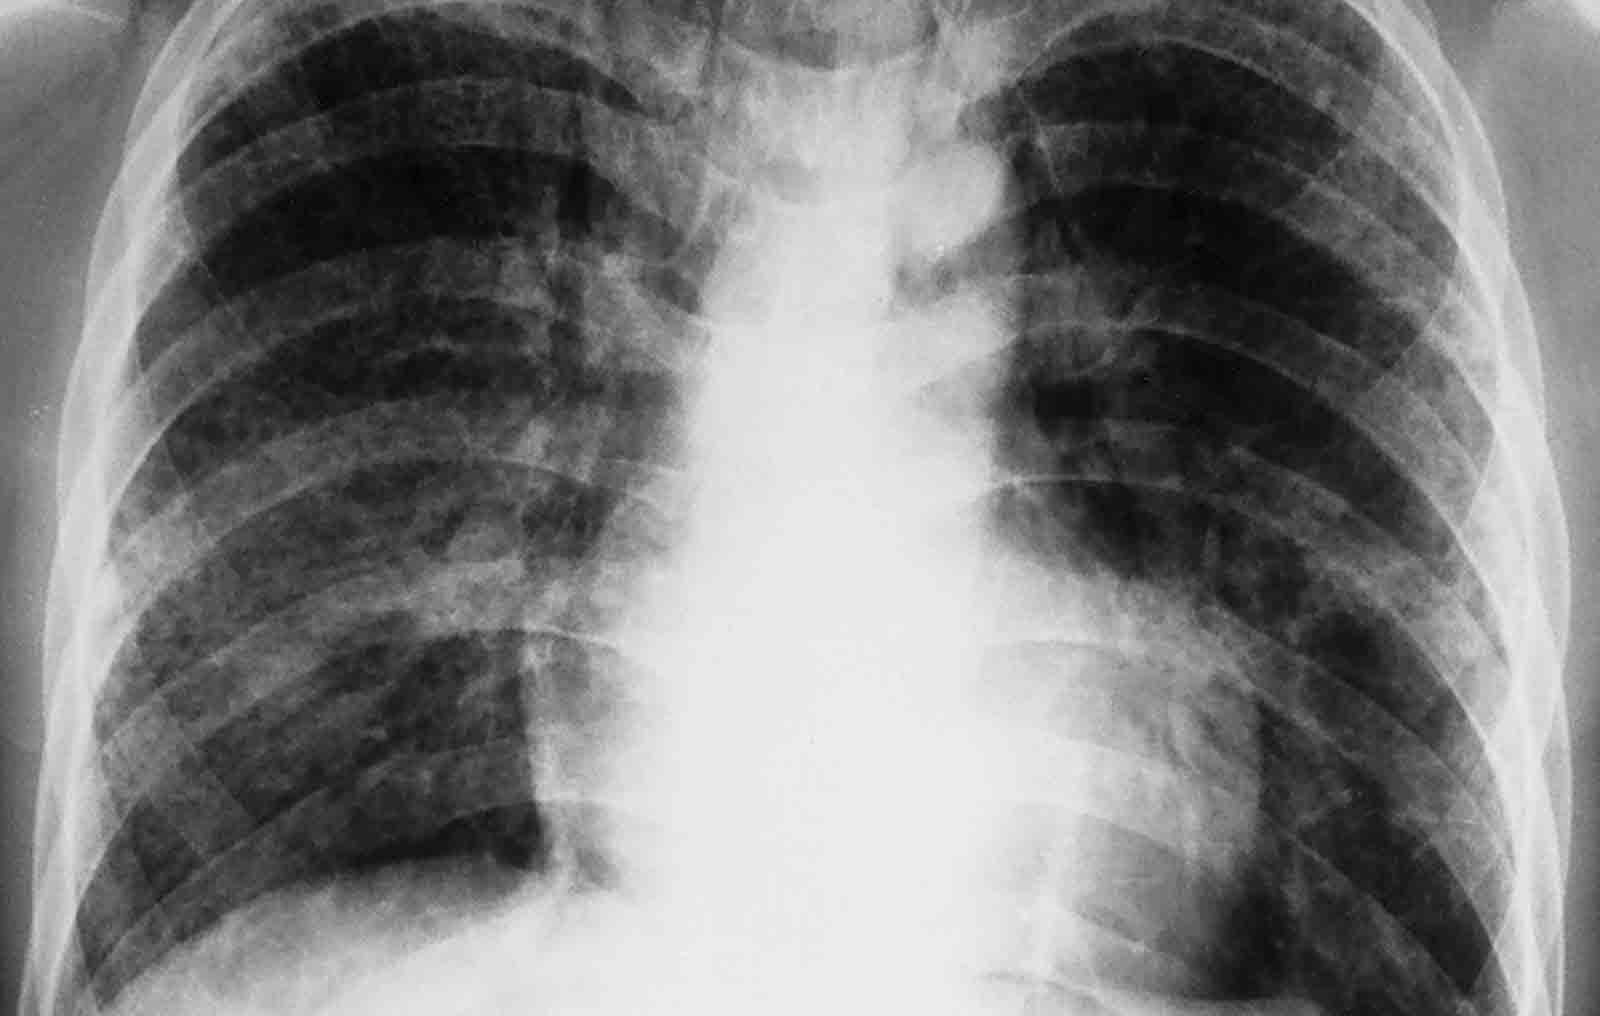

El Universal.- El director de Epidemiología de Salud Miranda, Miguel Viscuña, afirmó que en la semana epidemiológica número 12, se registró un incremento de los casos de infecciones respiratorias agudas en la Red Francisco de Miranda. Detalló que hubo un ascenso de 30%, al pasar de 523 casos en el reporte anterior a 730 en la actual medición.

Señaló que los Altos Mirandinos fue la región que contabilizó la mayoría de los casos al sumar 448, lo que representa 61,37% del total de pacientes que presentaron la afección, que está motivada fundamentalmente por dos elementos.

En primer lugar recordó que en esta época comienza la circulación de agentes infecciosos, tipo influenza, provenientes del hemisferio Sur y, en segundo lugar, la gran cantidad de gases lacrimógenos usados por los Cuerpos de Seguridad del Estado para disuadir protestas, así como también la quema de basura y combustibles plásticos de barricadas.

Viscuña indicó que estos gases de contenidos químicos y tóxicos han aumentado reportes, tanto para este tipo de infecciones como para los de cuadros agudos de asma. Ante tales afecciones, la Red Francisco de Miranda se mantiene alerta tanto para las reacciones de alergia como para los pacientes que tengan una enfermedad pulmonar de base. Así como para aquellos que adquieran influenza.